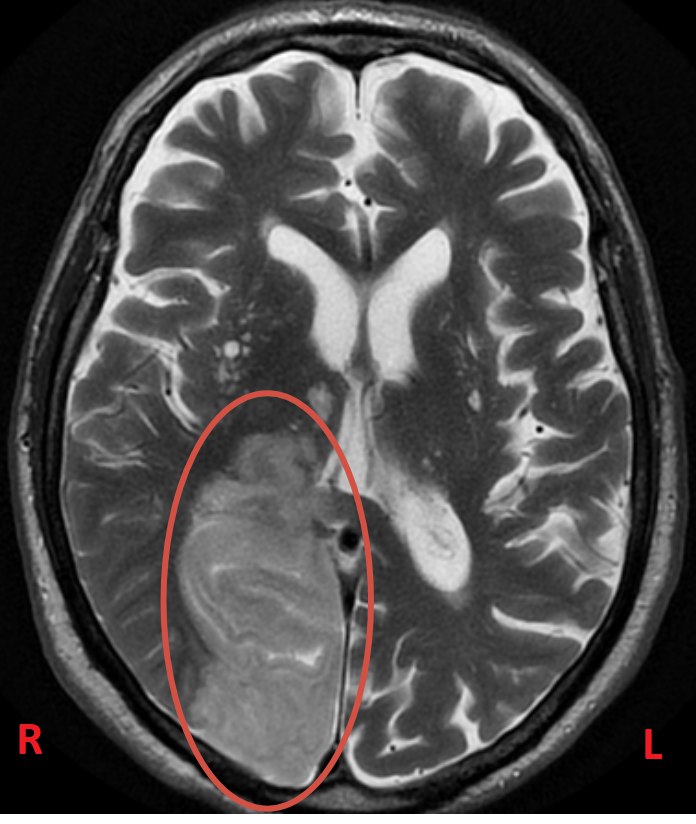

В нашем отделении уже через час была выполнена МРТ головного мозга, и диагноз подтвердился: острое нарушение мозгового кровообращения (инсульт).

В нашем случае МРТ показала инсульт в правой затылочной доле (в бассейне правой задней мозговой артерии).

Пациент не ослеп на левый глаз — он просто перестал видеть левую сторону пространства, при том что глаза оставались абсолютно здоровыми.